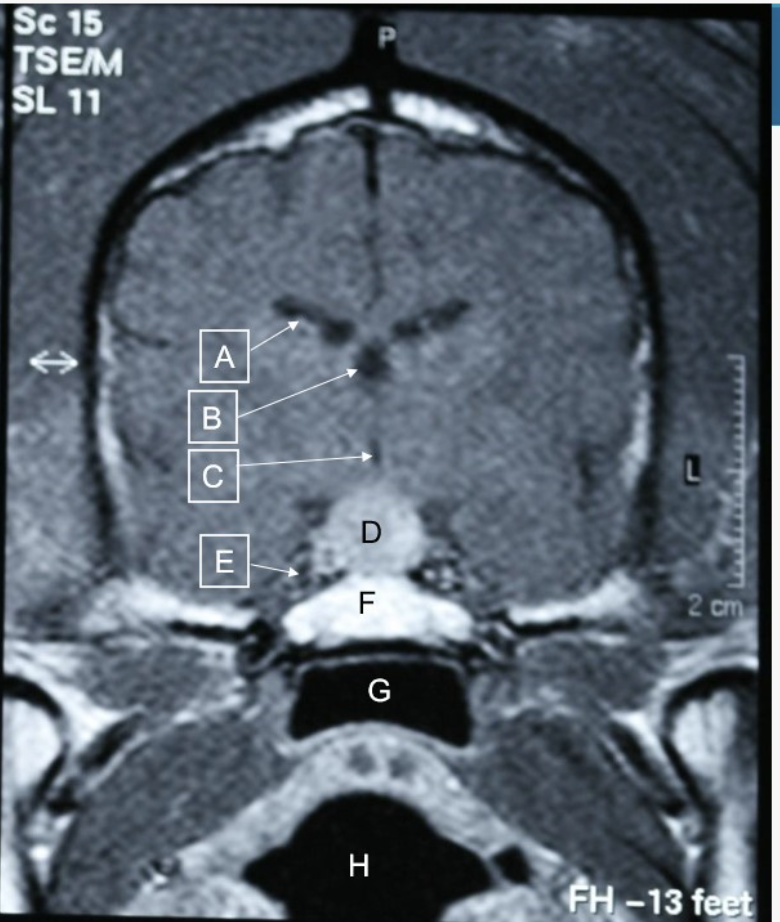

Q

Are there any pathological findings in this MRI of dogs head

A

pituitary mass at D